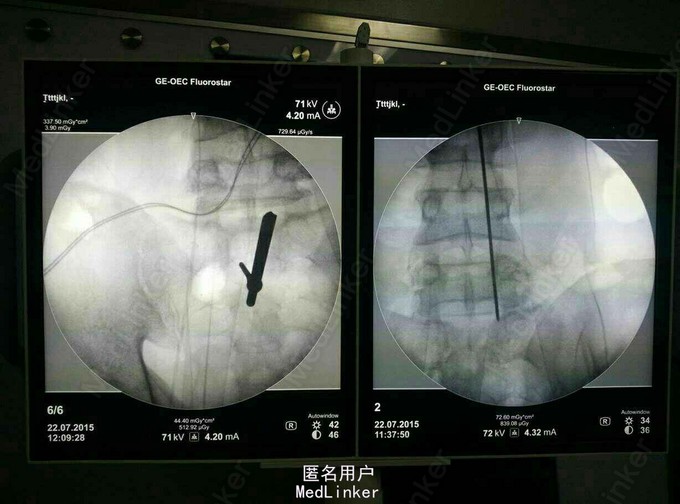

诊断:L5S1椎间盘脱出(向上高度游离) 治疗:后路经椎板间入路椎间孔镜下髓核摘除,射频消融。